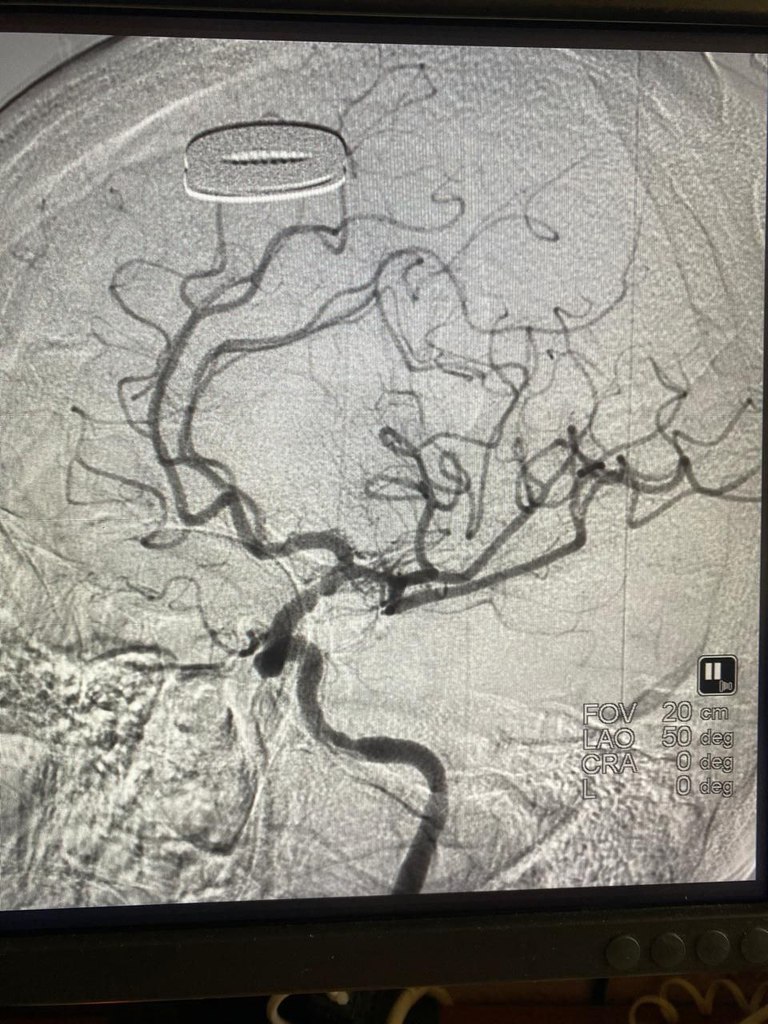

При поступлении отмечалось нарастание отрицательной неврологической динамики: парез мышц одной половины тела, потеря речи, угнетение сознания. Женщину экстренно подали в рентген-операционную, где была проведена успешная операция по удалению тромба и восстановлению мозгового кровотока.

Операция спасла женщину, как минимум, от тяжёлой инвалидности. У пациентки восстановились сознание и речь.